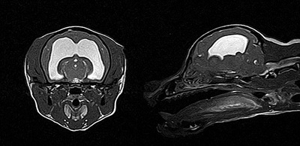

강아지 MRI는 반려동물의 신경계 질환이나 뇌, 척수, 관절 등의 정밀 진단에 매우 유용한 영상 검사입니다. 주로 경련, 사지마비, 뇌염, 뇌종양, 디스크 질환, 수두증 등 신경계 증상이 있을 때 시행하며, 방사선을 사용하지 않고 강한 자기장을 이용해 신경 조직의 변화를 상세하게 볼 수 있습니다. 검사 시 강아지를 전신마취해야 하며, 마이크로칩 같은 금속성 물질이 있으면 제거 후 촬영하는 것이 좋습니다.

- 뇌종양은 MRI에서 뇌 내에 명확한 종괴(종양 덩어리)가 보이며, 조영제 주입 후 해당 부위가 강하게 증강되는 특징이 있습니다. 종양 주변에 부종이나 뇌조직 압박 증상이 동반돼 보이며, 위치와 크기가 확인됩니다. 뇌종양은 노령견에서 발작과 함께 행동 변화, 균형 장애, 시각장애 등의 신경학적 증상이 나타납니다.

- 반면 간질 자체는 구조적 이상을 동반하지 않는 특발성 간질일 경우 MRI에서 이상 소견이 없거나 미약한 변화를 보입니다. 그러나 구조적 간질의 경우에는 뇌염, 뇌 손상, 뇌기형, 뇌출혈 등 뇌 조직에 국소적 변화가 MRI에 나타나기도 합니다. 간질 증상은 반복적 경련이 주로 특징이며, MRI를 통해 간질의 원인이 되는 뇌 조직 손상 여부를 평가합니다.

결론적으로, MRI는 뇌 안에 실제 종양 덩어리 및 주변 조직 변화를 뚜렷이 보여주며, 간질은 뇌종양과 달리 종괴 없이 경련 발생 원인에 따른 뇌 조직 변화를 확인하는 데 도움을 줍니다. 따라서 MRI 영상 소견과 임상 증상을 종합해서 뇌종양과 간질을 구분하고, 이에 맞는 치료 계획을 세우게 됩니다.